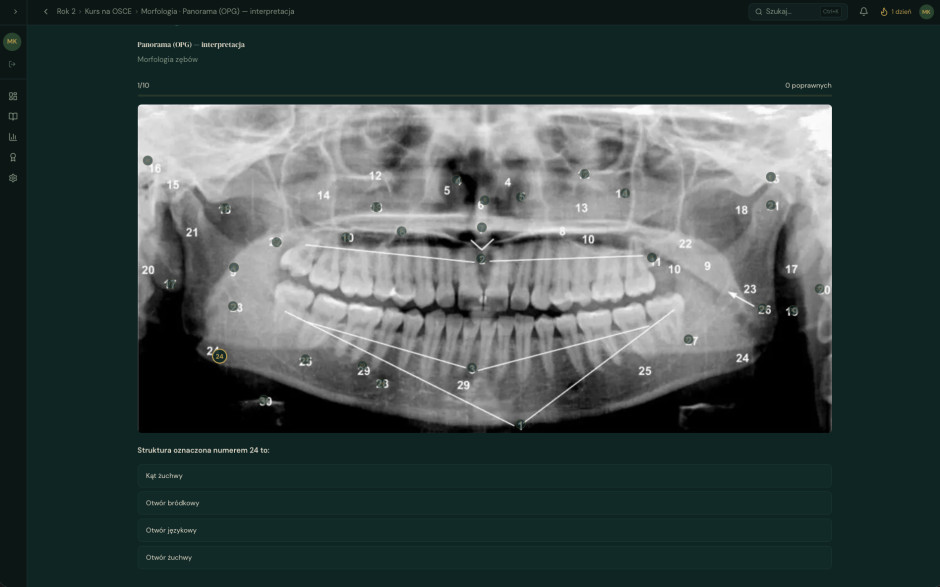

Zenit Labs tworzy inteligentne platformy edukacyjne szyte na miarę polskiego rynku medycznego. Łączymy najnowsze osiągnięcia sztucznej inteligencji z głęboką znajomością realiów kształcenia stomatologów i lekarzy budując narzędzia, których do tej pory po prostu nie było. Nasz flagowy produkt, Kurs na LDEK, to pierwsza w Polsce w pełni adaptacyjna platforma do przygotowania do egzaminów dla młodych dentystów. Autorski silnik AI analizuje każdego użytkownika indywidualnie: słabe punkty, tempo uczenia się i harmonogram, budując spersonalizowaną ścieżkę do zdania egzaminu w czasie rzeczywistym. Prowadzimy aktywne prace B+R nad kolejnymi modułami: symulacjami klinicznymi, systemem rekomendacji opartym na dużych modelach językowych oraz ekspansją na egzaminy specjalistyczne i rynki CEE. Setki aktywnych użytkowników. Dziesiątki tysięcy sesji. Mierzalna poprawa wyników.